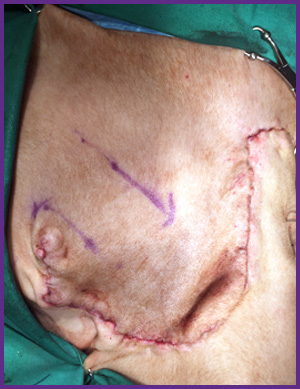

我們提供留院服務並擁有相應的治療設施,亦是小數備有CT電腦掃描及MRI磁力共振等大型醫療儀器的診所及醫院。